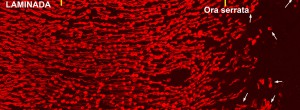

Hyporeflective wedge-shaped band in geographic atrophy secondary to age-related macular degeneration: a little-understood spectral domain optical coherence tomography finding.